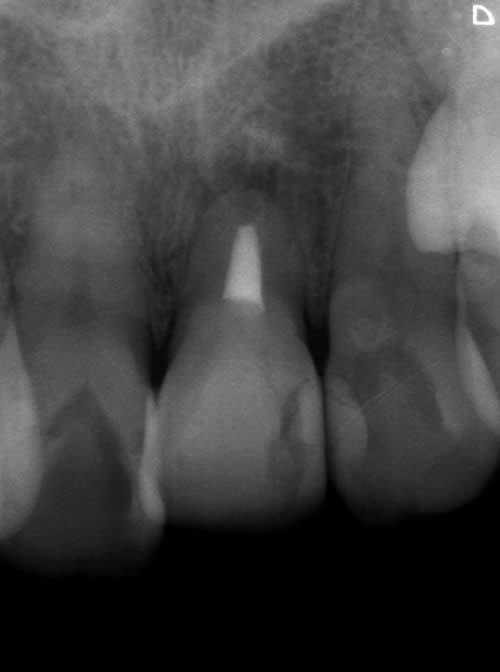

< 症例1 >

- 治療期間:6ヶ月

- 治療回数:8回

- 治療歯数:1歯

- 費用:インプラント治療:45万円 上部セラミック:89,000円

- リスク:メンテナンスを怠ると、インプラント周囲炎になる可能性があります。

- インプラント手術には合併症が伴う場合があります。

- 治療期間は治癒の状態により前後する場合があります。